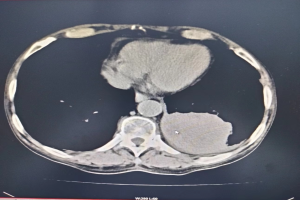

该患者罹患晚期肺癌,此次因发热伴呼吸急促入住区人民医院呼吸与危重症医学科。患者入院后,主要症状为呼吸急促,稍活动即感气喘,日常生活(穿衣、吃饭等)能力受限,胸部CT提示左肺下叶肿块,结合临床符合肺癌伴周围阻塞性炎症的特点,考虑肿瘤新生物堵塞管腔致呼吸急促,发热与阻塞性肺炎有关。经医生全身评估后,明确患者已无手术机会,其本人及家属均拒绝接受放化疗及免疫治疗。

术前胸部CT评估